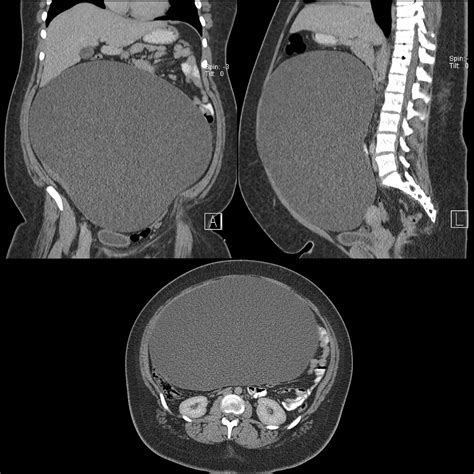

Learn why an Ovarian Cyst CT scan is a critical diagnostic tool for identifying pelvic masses. Discover how medical imaging helps radiologists evaluate cyst size, density, and potential complications. Understand what to expect during your procedure, how this screening assesses risk levels, and why accurate scan results are essential for determining the most effective ovarian health treatment plan.